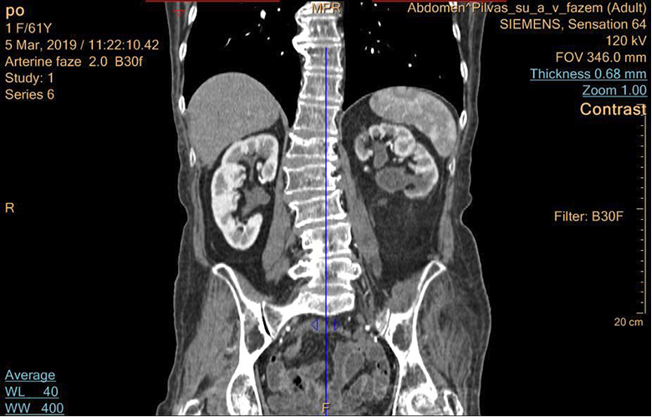

Po mėnesio pacientei pašalintas endostentas iš kairiojo šlapimtakio. Pooperaciniu periodu pacientė kairiojo juosmens skausmų nejaučia, šlapinasi gerai. Pacientei likę minimalūs pooperaciniai randai (žr. 3 pav.). 2019-03-05 atlikta kontrolinė KT – kairiojo inksto geldelės prasiplėtimas sumažėjęs iki 19 mm (žr. 4 pav.). Tyrimuose – kreatininas (66 µmol).

4 pav. Pacientės inkstų KT po operacijos praėjus dviem mėnesiams